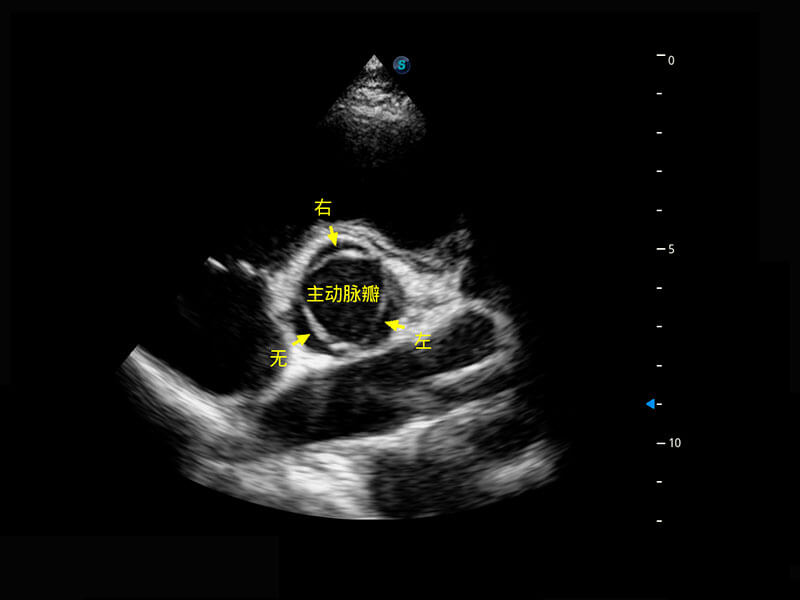

右室双出口